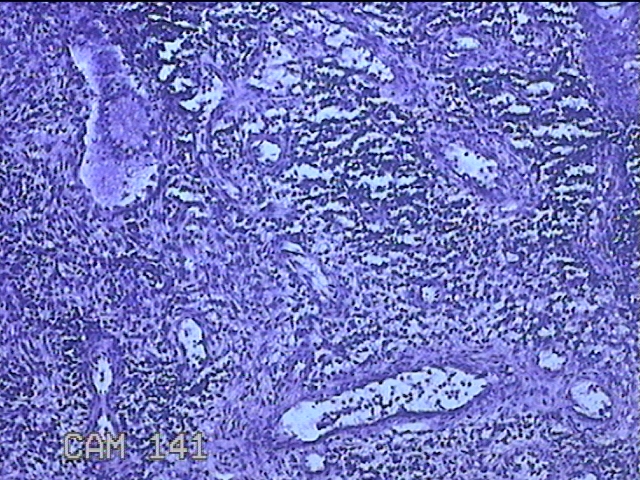

性别

女

年龄

36岁

临床诊断

宫颈赘生物

一般病史

发现宫颈赘生物1个月。

标本名称

大体所见

灰白暗红色肿物1x0.7x0.2cm一个,表面糜烂。

图4